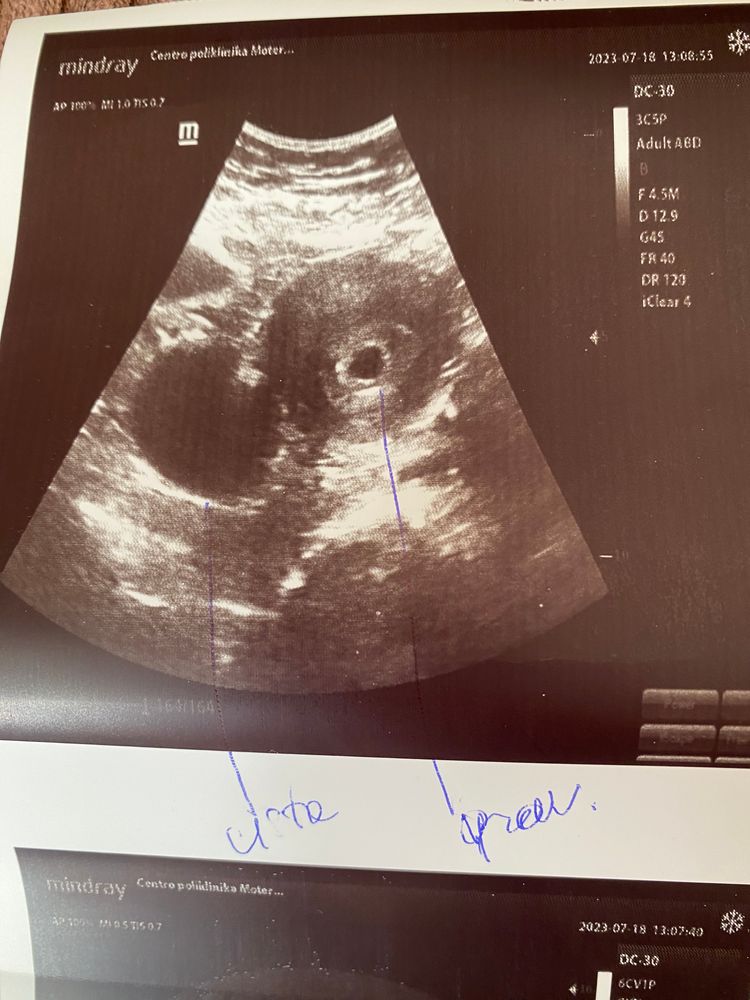

Может есть кто знает как позначены размеры плодного яйца на фото с узи?.. Узистка сказала срок 4-5 недель и нету ничего кроме плодного яйца( все нормально, оно появится позже если все норм, я это все знаю), больше ничего не скпзала